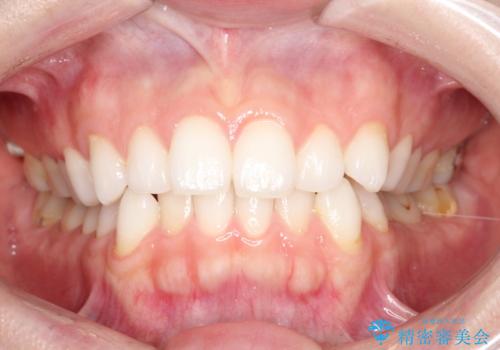

前歯のがたつきをインビザラインで目立たず矯正治療

- 上下の前歯のがたつきを主訴に来院されました。

目立たない装置がご希望で、インザラインによるマウスピース矯正にて治療を行うこととなりました。